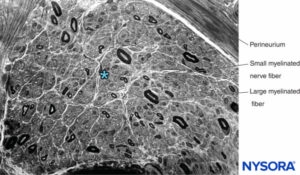

In a peripheral nerve, nerve fibers and their supporting Schwann cells are held together by connective tissue organized into three distinctive components that have specific morphological and functional characteristics. The epineurium forms the outermost connective tissue of the peripheral nerve, the perineurium surrounds each nerve fascicle separately, while the individual nerve fibers are embedded in the endoneurium (Figures 10 to 13).

FIGURE 11. Semithin section of human sural nerve fixed in osmium tetroxide. The myelin sheaths are preserved and stained black.